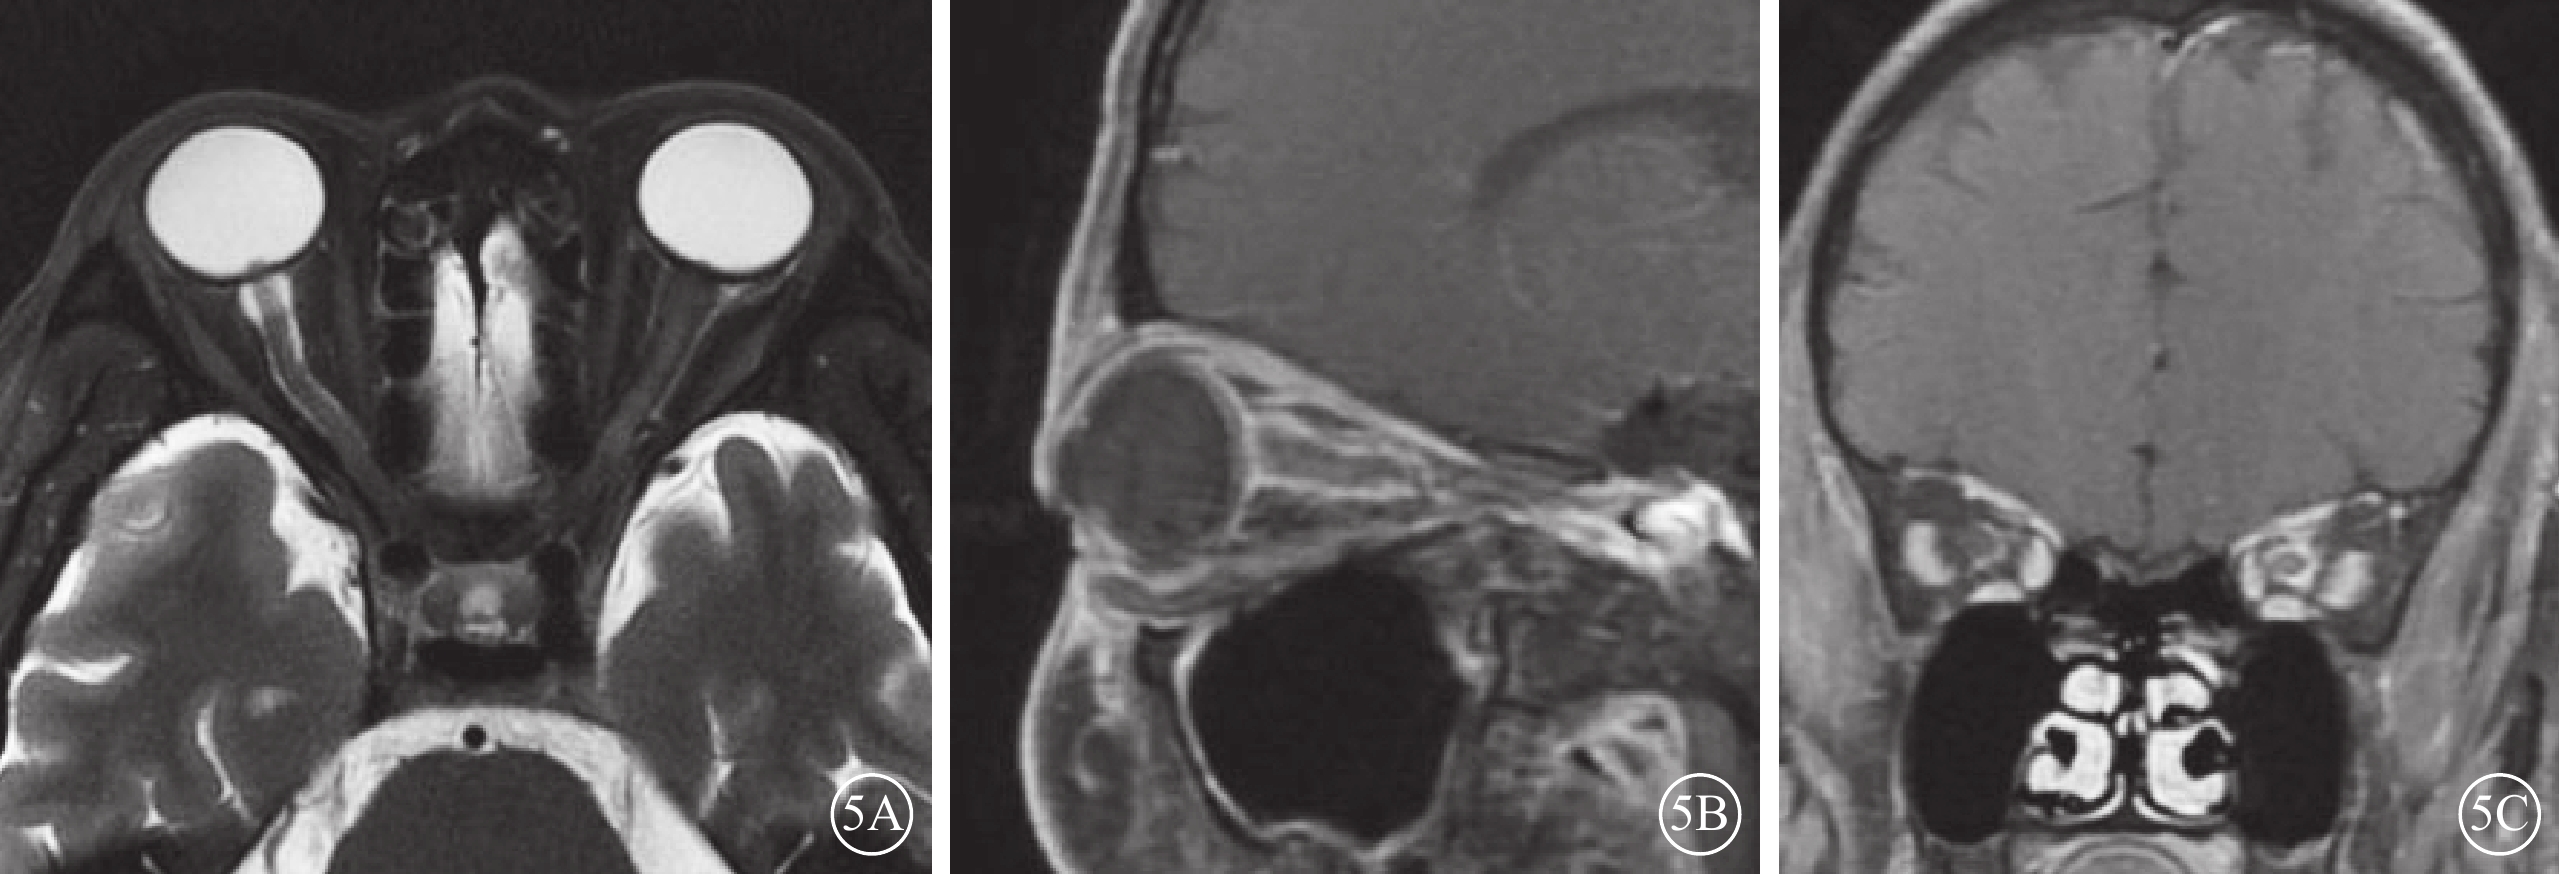

ION患眼,T2加權像視神經彌漫性或局限性增粗,伴或不伴鞘膜間隙增寬;T1加權像造影劑增強序列可見視神經鞘膜強化,其中軸位像示視神經呈雙軌樣強化(雙軌征),冠狀位像示視神經呈環形強化(袖套征),但視神經實質無明顯增粗或強化(圖5)。其中,繼發于全身性惡性腫瘤的13例17只眼中,合并眼外肌等眶內軟組織浸潤改變1例1只眼;繼發于眼眶周圍惡性腫瘤的7例9只眼,均可見與眶周原發性惡性腫瘤相延續、且累及視神經的軟組織腫物(圖6)。合并癌性腦膜炎的4例6只眼,均可見腦膜局灶性或彌漫性增厚和強化;合并顱內轉移灶的4例4只眼,均可見腦實質內散在分布的點狀或灶狀長T2信號病灶伴強化。

圖5

淋巴瘤繼發浸潤性視神經病變患者(圖1患者)眼眶核磁共振成像檢查像 5A示T2加權像,雙眼視神經增粗,右眼視神經鞘膜間隙增寬。5B、5C示T1加權像造影劑增強序列,矢狀位可見視神經鞘膜強化呈雙軌征(5B);冠狀位可見左眼視神經鞘膜增粗和明顯強化,右眼視神經鞘膜輕度強化,呈袖套征(5C);雙眼視神經實質無明顯增粗或強化